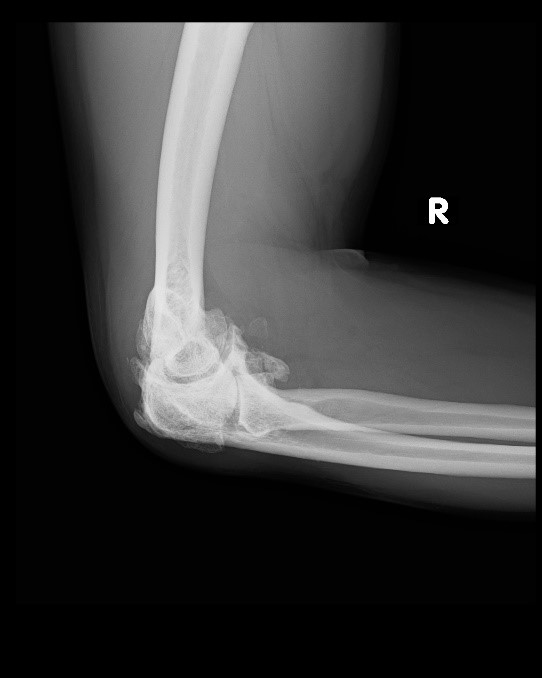

from gioqvuehk.blob.core.windows.net

Arthritis Elbow Treatment at Jose Norman blog

Arthritis Elbow Treatment at Jose Norman blog Can Elbow Arthritis Be Cured It could be elbow arthritis. The elbow can be affected by osteoarthritis but it is less common than in other joints. Learn more about the symptoms, home remedies and treatments. How is arthritis of the elbow treated? Find out how to prevent. Learn about the common causes of elbow pain, such as strained or inflamed soft tissues, and how to. Can Elbow Arthritis Be Cured.